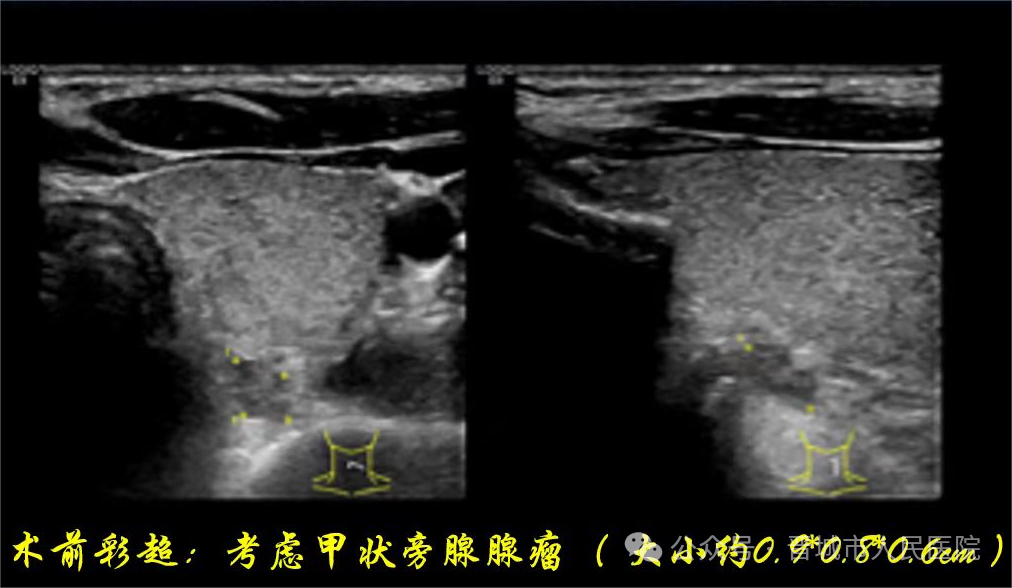

王丽云主任结合患者既往临床资料,为其行精准超声复查,发现甲状腺左侧叶中部后方低回声结节,结合PET-CT影像学特征及实验室结果,明确诊断为原发性甲状旁腺功能亢进(甲状旁腺腺瘤),且符合微波热消融指征。

2026年2月,患者疼痛加重,再次就诊于长治医学院附属和平医院,复查提示甲状旁腺激素84.08pg/mL、25-羟维生素D11.4ng/mL(明显缺乏)、磷0.80mmol/L、血钙2.68mmol/L(持续偏高);彩超显示甲状腺左侧叶后方结节临近血管神经,当地医生告知无法实施消融术。陷入困境的患者,辗转来到我院内分泌科寻求精准诊治。